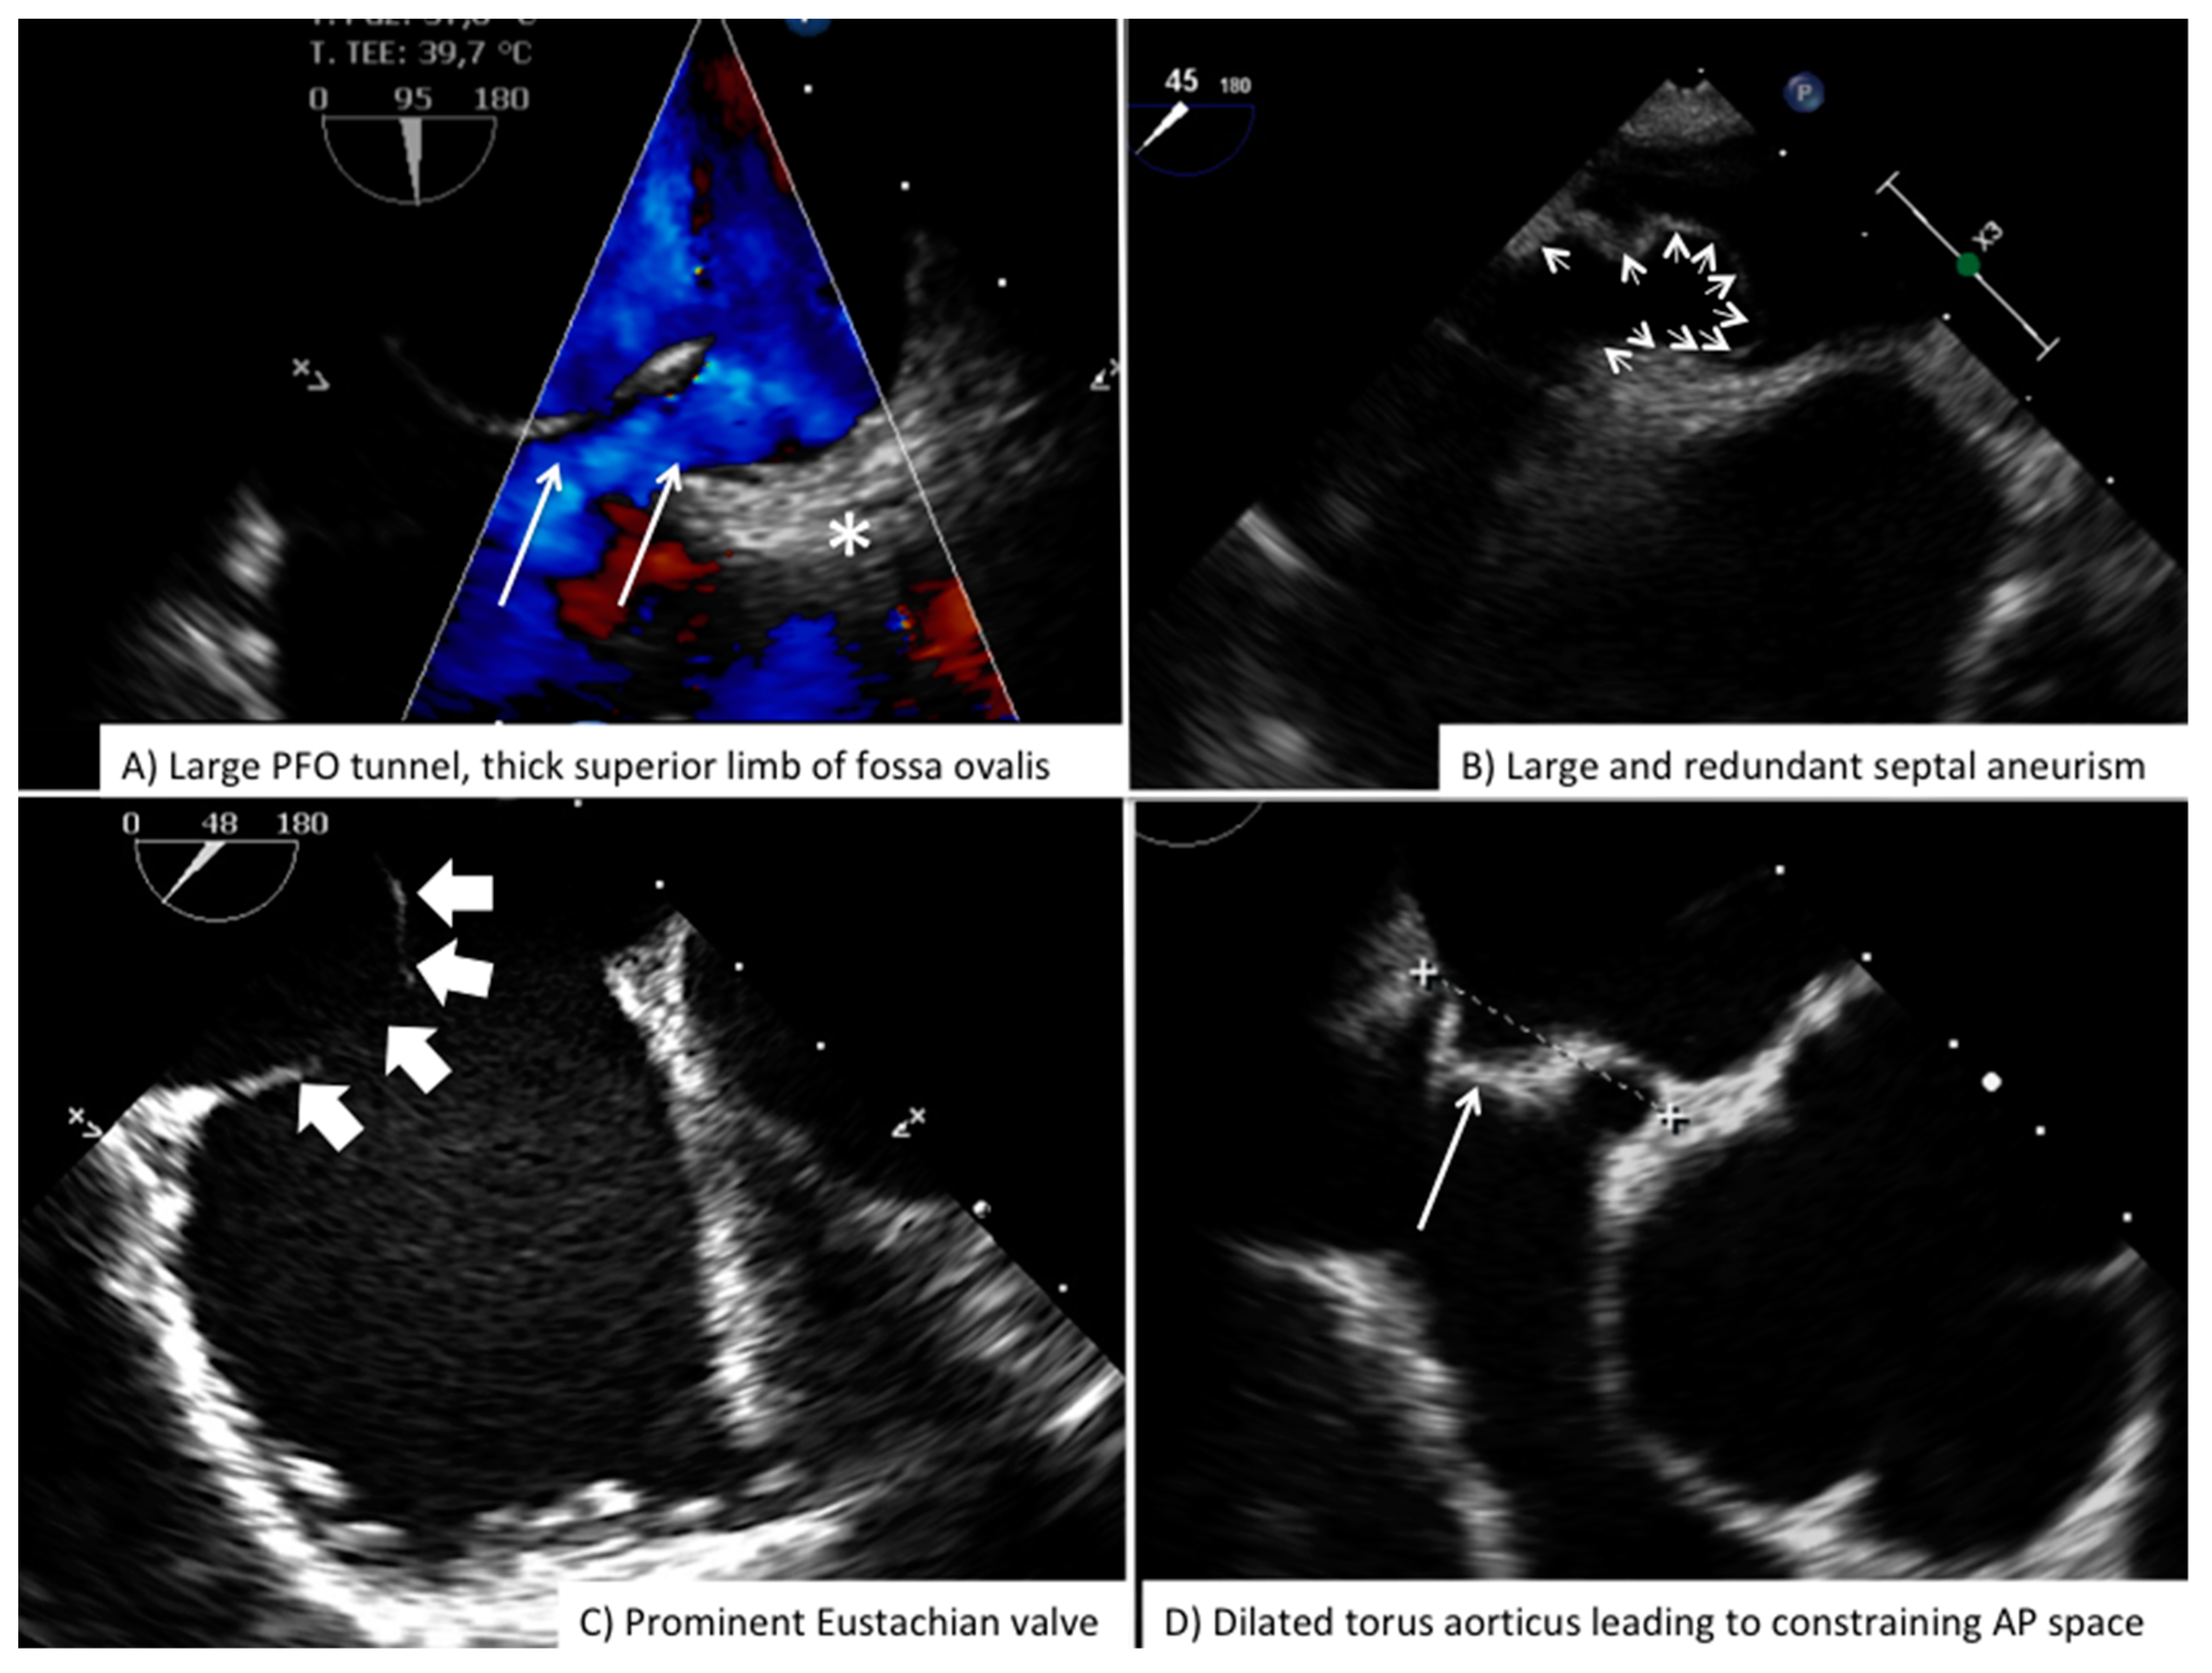

| Before vascular access | Free LA appendage Normal aortic and mitral valve No intracardiac mass Atrial septal aneurysm Eustachian valve Chiari Network Accessory fenestration Antero-posterior septal distance | Free LA appendage No significant mitral valve disease Atrial septal aneurysm Eustachian valve Chiari Network Assess border features Multifenestrated ASD Confirm normal pulmonary vein anatomy Bidimensional and color-based shortest and largest ASD diameter 3D-based shortest and largest ASD diameter |

| After vascular access | Confirm right-to-left shunt at intracardiac bubble study Confirm correct tunnel wiring Confirm wire position in the proper pulmonary vein PFO tunnel amplitude and length | Confirm wire position in the proper pulmonary vein Balloon sizing in stop-flow condition |